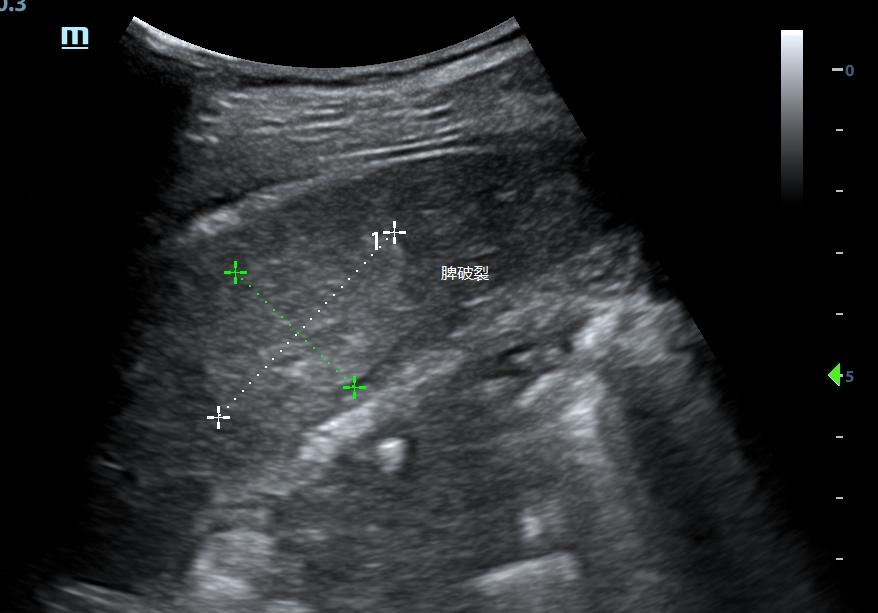

不同设备条件下得到的超声图像可能有很大差别,特别是肾脏血肿、肝脾挫伤。

对于外伤后患者,大量肾周血肿、明显的肝脾破裂谁都会看,但少量的肾脏血肿,隐匿性的肝肾挫伤或破裂,增益过高很可能就直接漏诊。

脾破裂

没有最合适的增益,只有反复调节的增益。

超声受气体、脂肪、组织密度等等等各种因素影响,同一台设备条件不一定适用所有人,每个患者都需要调节至显示清楚的条件。

对于同一个患者,不同增益下可能会给你带来不一样的信息,如果还有不会调节设备的小伙伴,可以阅读这里:0基础入门,超声设备的使用和调节